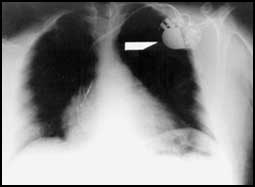

اجرى مركز الأمير سلطان لمعالجة أمراض وجراحة القلب للقوات المسلحة ثاني عملية على مستوى العالم بعد البرازيل وذلك بإجراء ثلاث عمليات لزراعة جهاز خاص لتنظيم انقباض البطين الايسر والايمن للقلب، استغرقت العملية اقل من ساعة وبتخدير موضعي وجميع المرضى غادروا المركز بعد ثلاثة أيام من اجراء العملية.

وقد قام بإجراء هذه العمليات الدكتور محمد بن علي حباب استشاري اول طب قلب للكبار ورئيس قسم كهربائية القلب وتنظيم ضربات القلب بمركز الأمير سلطان لمعالجة امراض وجراحة القلب للقوات المسلحة، حيث ذكر بقوله بأن الطريقة الجديدة التي تم اجراؤها مؤخرا في المركز لثلاثة مرضى تتركز على توصيل التيار الكهربائي الى البطين الأيسر عن طريق زراعة التوصيلات الكهربائية التي تصل مباشرة عبر المنطقة المتوسطة بين البطين الأيمن والأيسر والتي تستغرق حوالي اقل من ساعة وبنجاح اكبر وبدون مضاعفات تذكر ونتائجها تؤدي الى تحسن ملحوظ في عمل عضلة القلب المصحوب في تحسن نسبة الارتجاع في صمامات البطين الأذيني والتي يتوقع ان تؤدي الى الحد من تقليل نسبة هذا التضخم، والطريقة الجديدة التي تكلفتها اقل بكثير من الطريقة التقليدية السابقة والتي تشتمل على زراعة توصيلات كهربائية الى البطين الايسر عن طريق الاوردة القلبية والتي تستغرق وقتا اطول يصل الى ثلاث ساعات ونسبة مضاعفات اكثر ونجاح اقل.